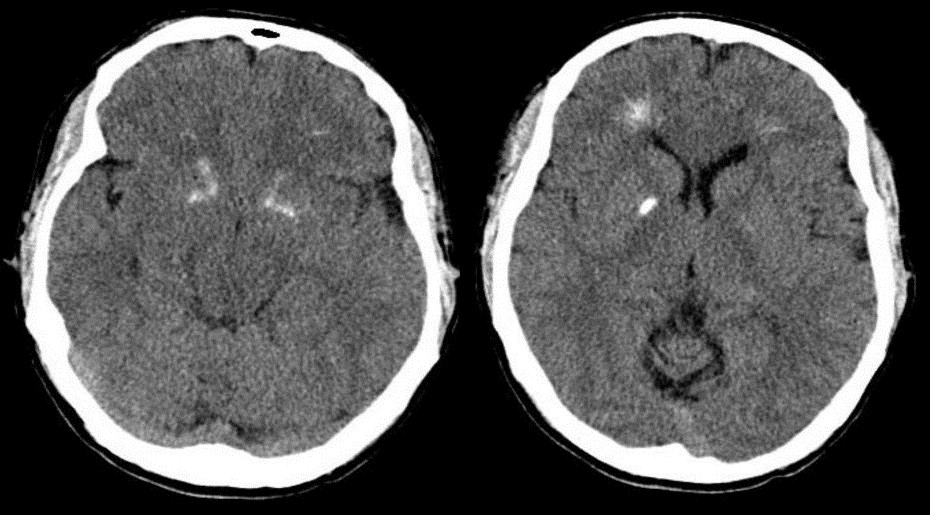

كما يقوم الطبيب أيضًَا بإجراء العديد من الاختبارات الخاصة بالدم لإظهار المستويات المنخفضة من الكالسيوم وعمل تصوير عن طريق الأشعة السينية والمقطعية للتعرف على عيوب القلب وكافة أعضاء الجسم الأخرى، بالإضافة إلى أن الطبيب يقوم بالفحص البدني للأذنين والعينين والمفاصل للكشف عن التشوهات.